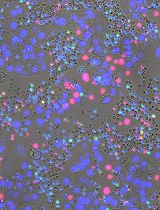

Figure 2. Plate map and example images following assaying of a GFP-LUHMES 384-well plate drug screen. A. Plate map showing the suggested arrangement of control wells and test compound wells. All wells are treated with rotenone except for “DMSO vehicle” wells. The colours represent the concentration in nM for each compound. B-D. Blue = DAPI, orange = TMRM, green = GFP, scale bars = 20 μm. Z stack maximum projection confocal images captured using the Opera Phenix High-Content Screening System from (B) a vehicle-treated DMSO control well, (C) a rotenone-treated DMSO control well and (D) a rotenone-treated positive control well (1,000 nM).

Figure 3. Analysis protocol selections using the Columbus Image Data Storage and Analysis System. A. “Find Neurites” selection using the Alexa 488 channel, see step 4c of the Data analysis protocol. B. “Find Image Region” selection using the Alexa 488 channel, see step 4h. C. “Select Population” using the segmented Mitochondria channel, see step 4l. The indented image shows a close up of the individual selections. D. “Find Nuclei” selection using the DAPI channel, see step 4q. All scale bars = 20 μm.